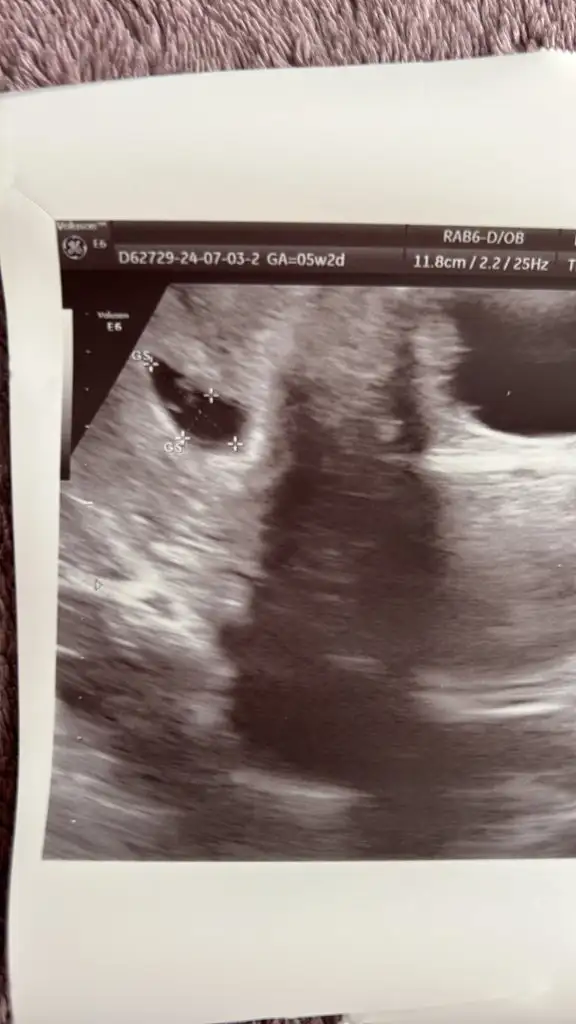

Merhaba merak ettim ama imkansız gibi sanki Karından 5 buçuk haftalık

Eklentiler

• 044C0D0B-70C5-4390-9357-9612AE42E7C4.webp

044C0D0B-70C5-4390-9357-9612AE42E7C4.webp

24,2 KB · Görüntüleme: 61